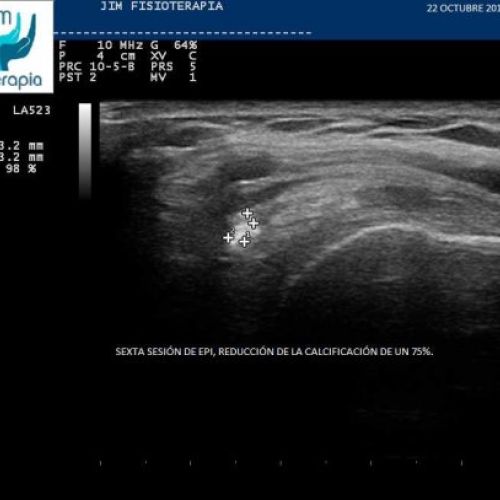

Tratamiento con EPI® de Tendinosis Calcificada del Supraespinoso

Imágenes del tratamiento de un caso de Tendinosis Calcificada del Supraespinoso mediante la terapia EPI® en Madrid.